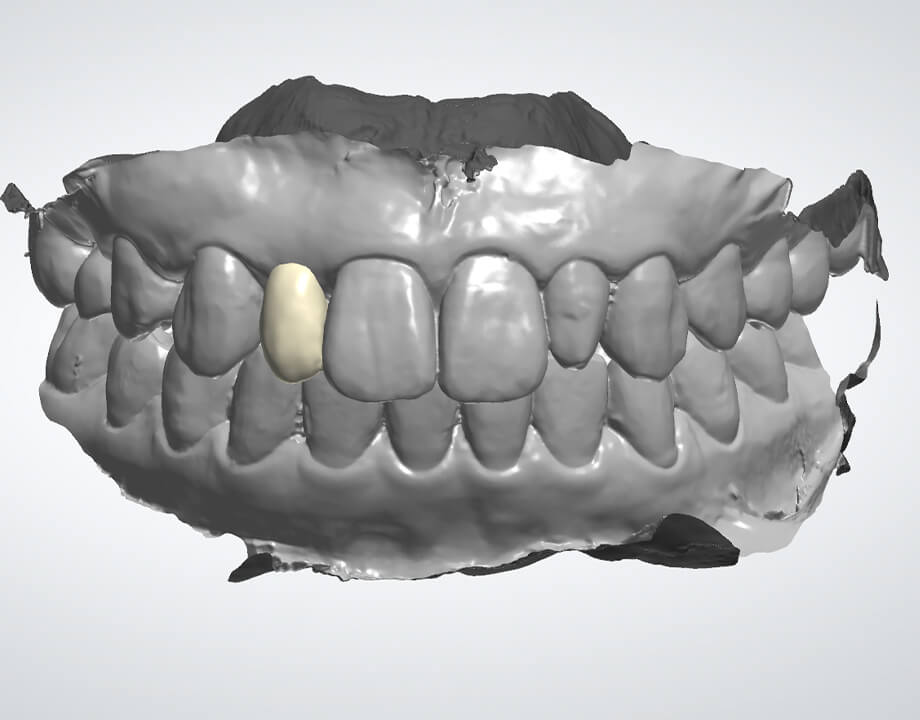

デジタルワックスアップ

→シュミレーション(SMOP)

→プロビジョナル

→最終補綴物(モノリシックジルコニアAGC)